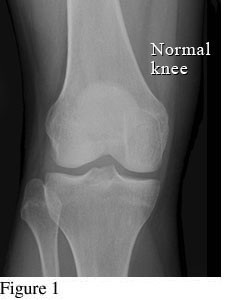

Hình ảnh so sánh giữa khớp bình thường và khớp bị thoái hóa khớp gối

Để phân biệt các giai đoạn của bệnh thoái hóa khớp gối, cần dựa vào phim X- quang theo tiêu chuẩn chẩn đoán thoái hoá khớp của Kellgren và Lawrence như sau:

Hình ảnh của khớp gối trên phim X-quang: Khe khớp hẹp nhiều, gai xương có kích thước lớn, đặc xương dưới sụn, đầu xương biến dạng rõ.

Thoái hóa khớp gối đã bước vào giai đoạn nặng, sụn khớp bị bào mòn và bong tróc gần như hoàn toàn để lộ đầu xương rõ rệt. Khoảng không gian chung giữa hai đầu xương thu hẹp đáng kể, gai xương ngày càng lớn, chất nhờn bôi trơn khớp giảm nên gây ra hiện tượng ma sát giữa hai đầu xương, gây đau nhức xương khớp nghiêm trọng. Người bệnh xuất hiện một loạt các triệu chứng đau nhức liên tục, cứng khớp, khó vận động khớp, khó đi lại… ảnh hưởng đến sinh hoạt. Theo thời gian, thoái hóa khớp gối có thể gây biến dạng khớp hoàn toàn, gây lệch trục khớp…